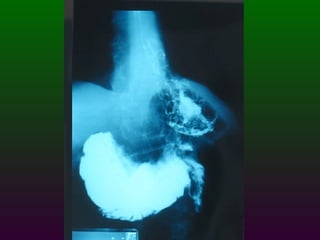

S.E.G.D.  Serie esófago gastro duodenal Definición  Estudio de doble contraste (bario) y aire del tracto digestivo superior. (esófago, estómago, duodeno)

SEGD La impresión radiológica básicamente se divide en tres limitados y un difuso Ulceración Estrechez Masa Compromiso difuso por ulceración y/o engrosamiento  parietal

SEGD ENFERMEDADES DEL ESTÓMAGO Y DUODENO DIVISIÓN ANATÓMICA DEL ESTÒMAGO CARDIAS  FONDO CUERPO  ANTRO  PÍLORO

SEGD ENFERMEDADES DEL ESTÓMAGO INFLAMACIÓN NEOPLASIAS: Pólipos benignos Carcinoma Linfoma Leiomiomas TRASTORNOS DIVERSOS: Gastritis atrófica Crónica:   Gastritis hipertrófica   Gastritis cáustica   Vólvulos